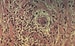

Case Presentation: During the COVID-19 pandemic, a 67- year-old female Japanese was undergoing treatment for interstitial pneumonia, diabetes mellitus, and hypertension at her local doctor. About 2 months ago, she was diagnosed with COVID-19 and went to a hotel for treatment, and her condition improved. But a month later, after her COVID-19 infection, she presented with a fever and cough and visited Yodogawa Christian Hospital in Osaka, Japan. The reverse transcription-polymerase chain reaction was negative. She underwent extensive radiological and laboratory investigations. Serologies revealed a high perinuclear-ANCA titer with a specific anti-myeloperoxidase antibody titer of 31.7 units/mL. We suspected ANCA-associated vasculitis and performed a renal biopsy. Renal biopsy showed evidence of crescentic glomerulonephritis, which was consistent with ANCA-associated vasculitis. The patient was referred to the Department of Rheumatology and Clinical Immunology for steroid pulse and cyclophosphamide treatment.